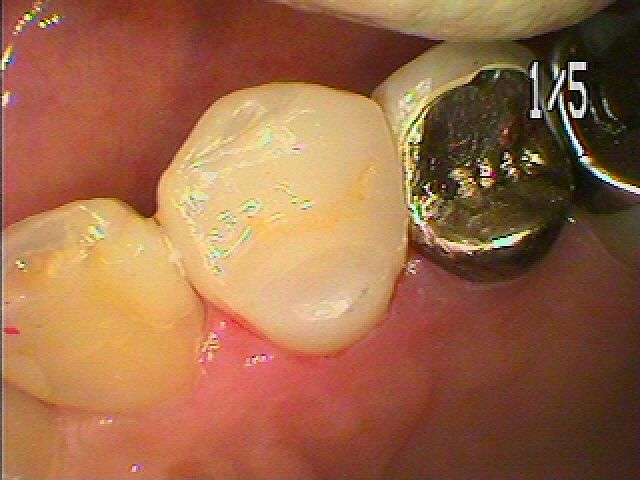

問題の歯になります

中は黒く虫歯にもなってきていました